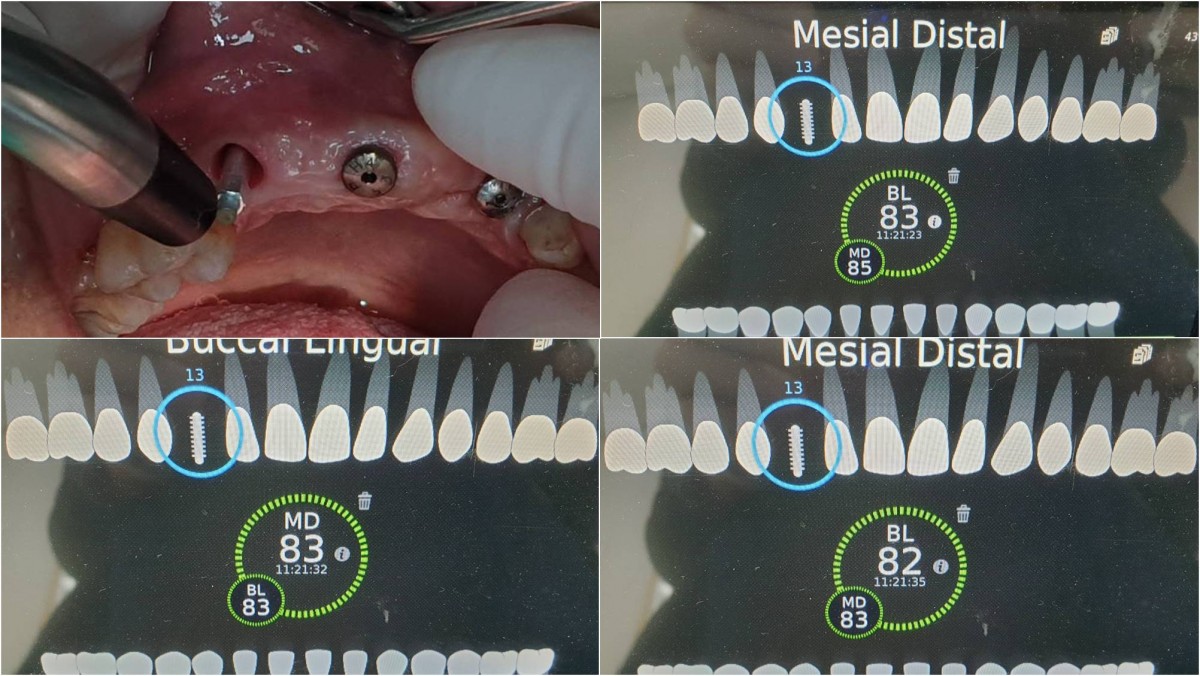

<GCpbc> A 58-year-old male is a patient undergoing implant installation in various parts. The old Br of the anterior maxilla has fallen

off and it is no longer possible to maintain it even temporarily, so a

treatment plan for the anterior teeth was made.